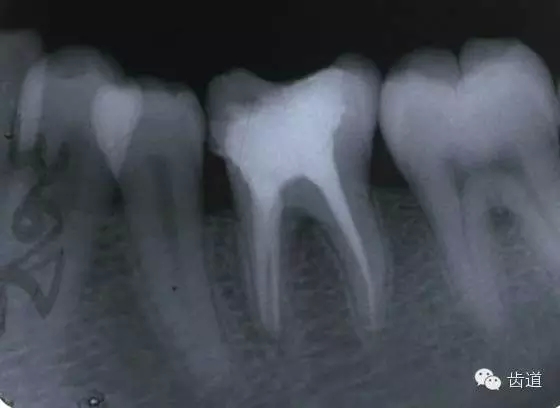

磨牙髓室頂、底距離接近時,易將髓底穿孔。

左下6底穿

左上6底穿